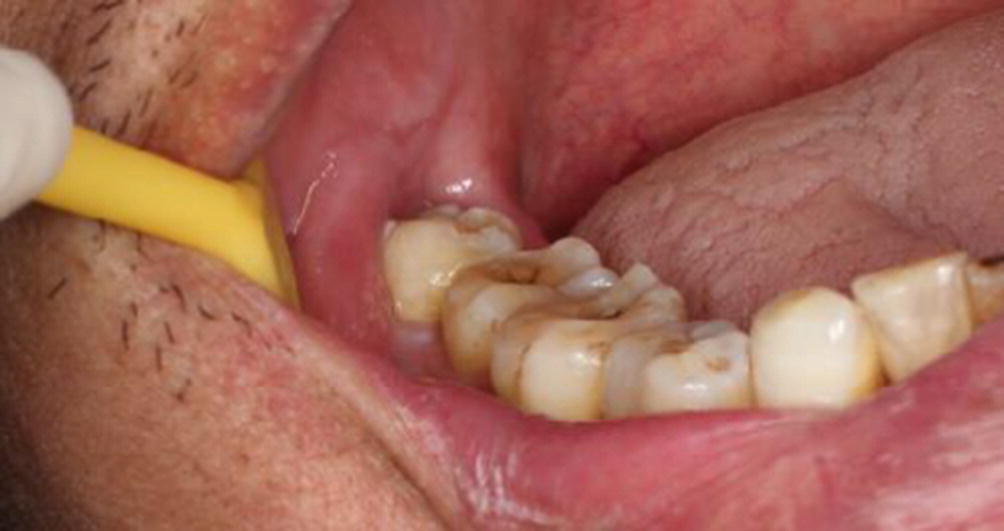

[caption id="attachment_7057" align="alignleft" width="401"]

gömülü diş[/caption] Gömülü diş diğer dişlerden ayrı olarak düzgün çıkamamış ve çene kemiği içinde kalmış olan diştir. Gömülü diş çekimi lokal anesteziyle yapılır. Gömülü dişler çene kemiğinde baskıya neden olarak çiğneme esnasında damak yaralanmalarına neden olmasının yanı sıra çekilmediği takdirde hızla çürümektedirler. Bu çürüme sonucunda da diş kökünde oluşan iltihap enfeksiyona dönüşerek kişide pek çok hastalığı da beraberinde getirebilir. Gömülü dişler en sık 20 yaş dişleri ve köpek dişleri olarak kendini göstermektedir. Gömülü dişlerin çekilmesi en çok önerilen bir ortodontik tedavi yöntemi olsa da dişlerin ne kadar gömülü olduğuna bağlı olarak düzeltme, çürük temizleme ve dolgu işlemi de yapılabilmektedir.